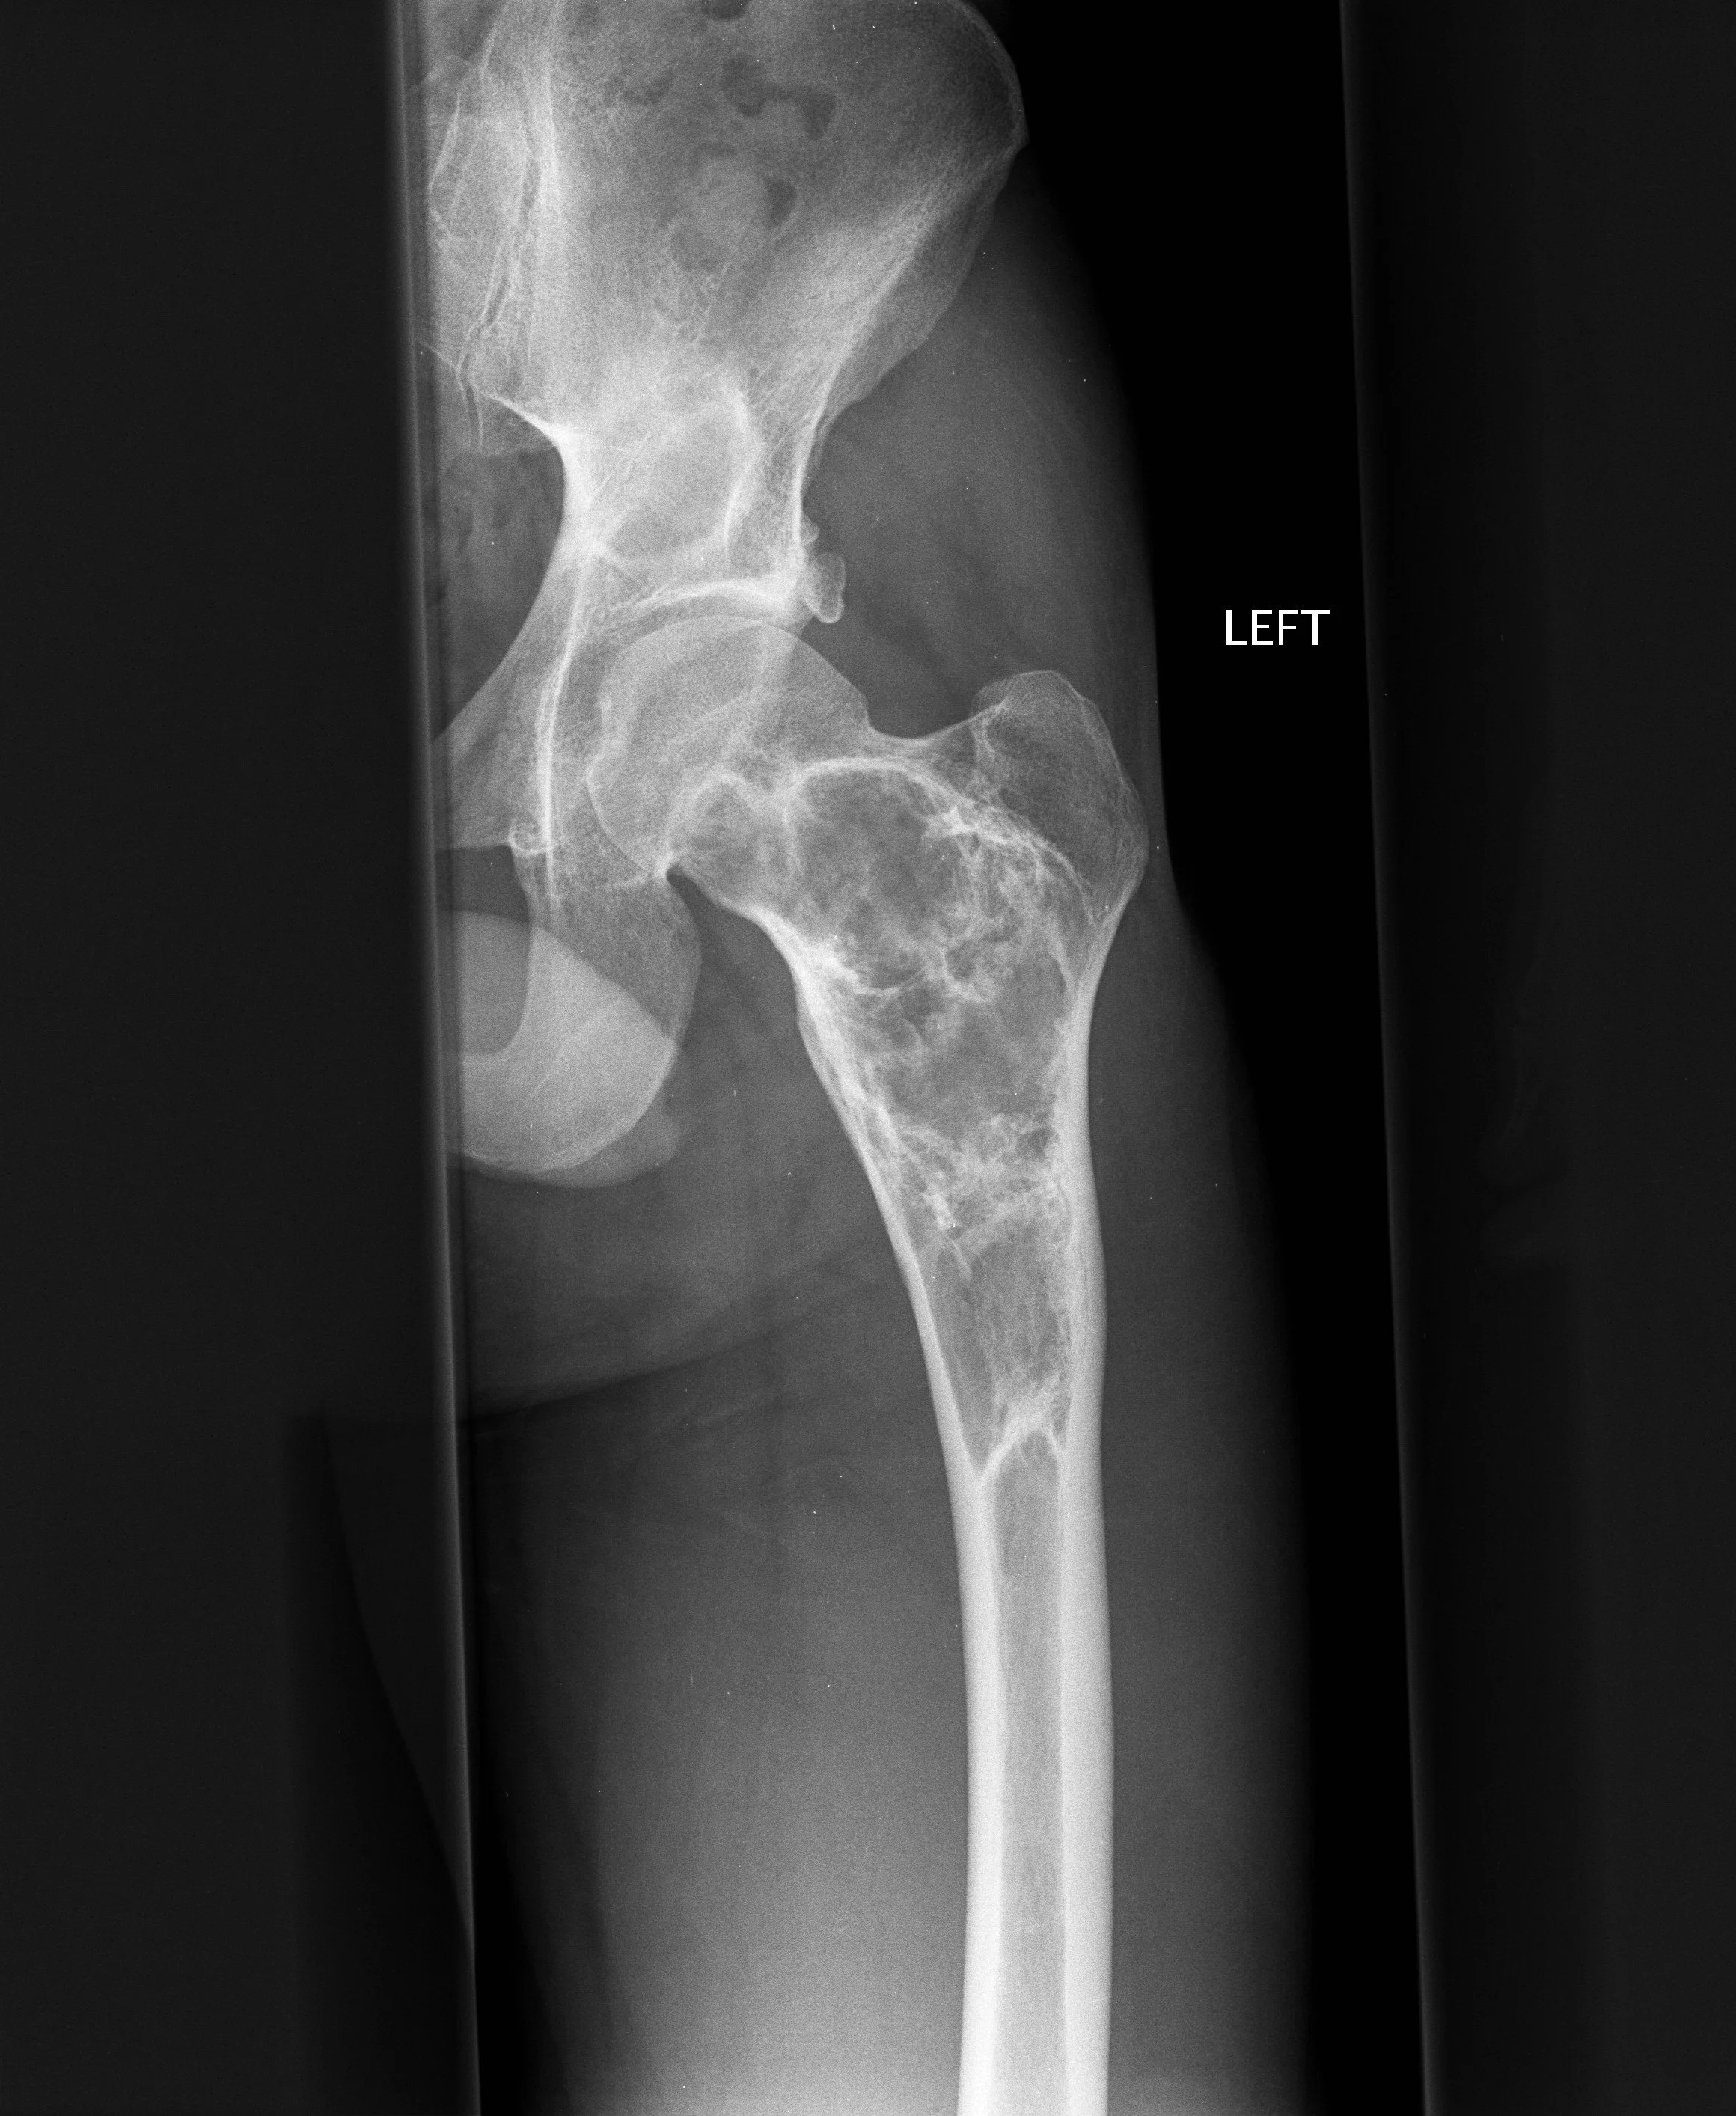

Pagets Disease

• Expansion of bone with thickened trabecula

• Multiple lesions

• Pelvis most commonly affected

• Almost never in fibula

• Blade of grass —> pointed appearance of lesion within the bone

• Secondary osteosarcoma can occur —> very bad